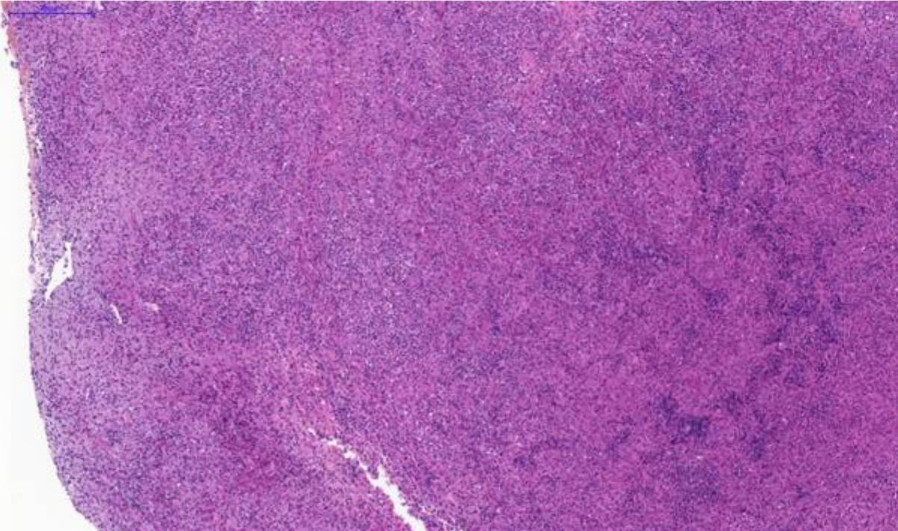

Fig. 1. Nasal tissue, feline. Section of the submitted sample showing severe pyogranulomatous inflammation. H&E stain. Scale bar = 1000 µm.

The connective tissue of the lamina propria of the nasal cavity was effaced by a diffuse, severe inflammatory infiltrate composed predominantly of numerous macrophages, often epithelioid, with abundant cytoplasm containing basophilic granular material. Interspersed among the macrophages were moderate numbers of neutrophils and fewer lymphocytes. A small section of trabecular bone was present, lined by reactive osteoblasts, neutrophils, and occasional macrophages and lymphocytes. The bone frequently contained a proliferation of elongated cells lacking evident atypia, arranged in bundles and embedded within a moderately collagenous stroma (reactive bone/connective tissue).